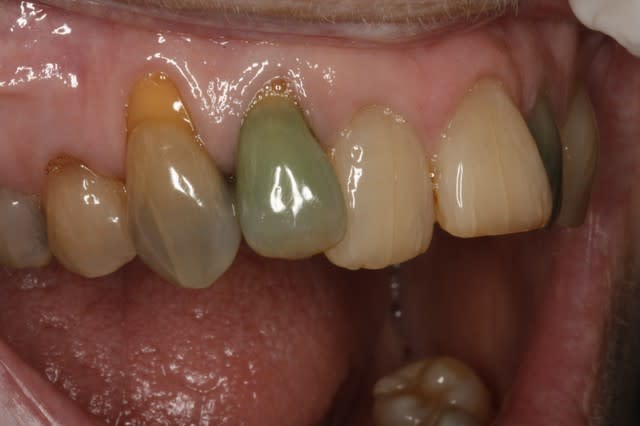

histoire de mettre un peu de couleurs dans ce post monotone...

un peu de vert :) c'est rare ....

Img 8509  custom  pv3zq2 - Eugenol

Cas classique d'allergie à la brosse à dents.

Je parie...pas de douleur ?

Un cas pour Borst ?